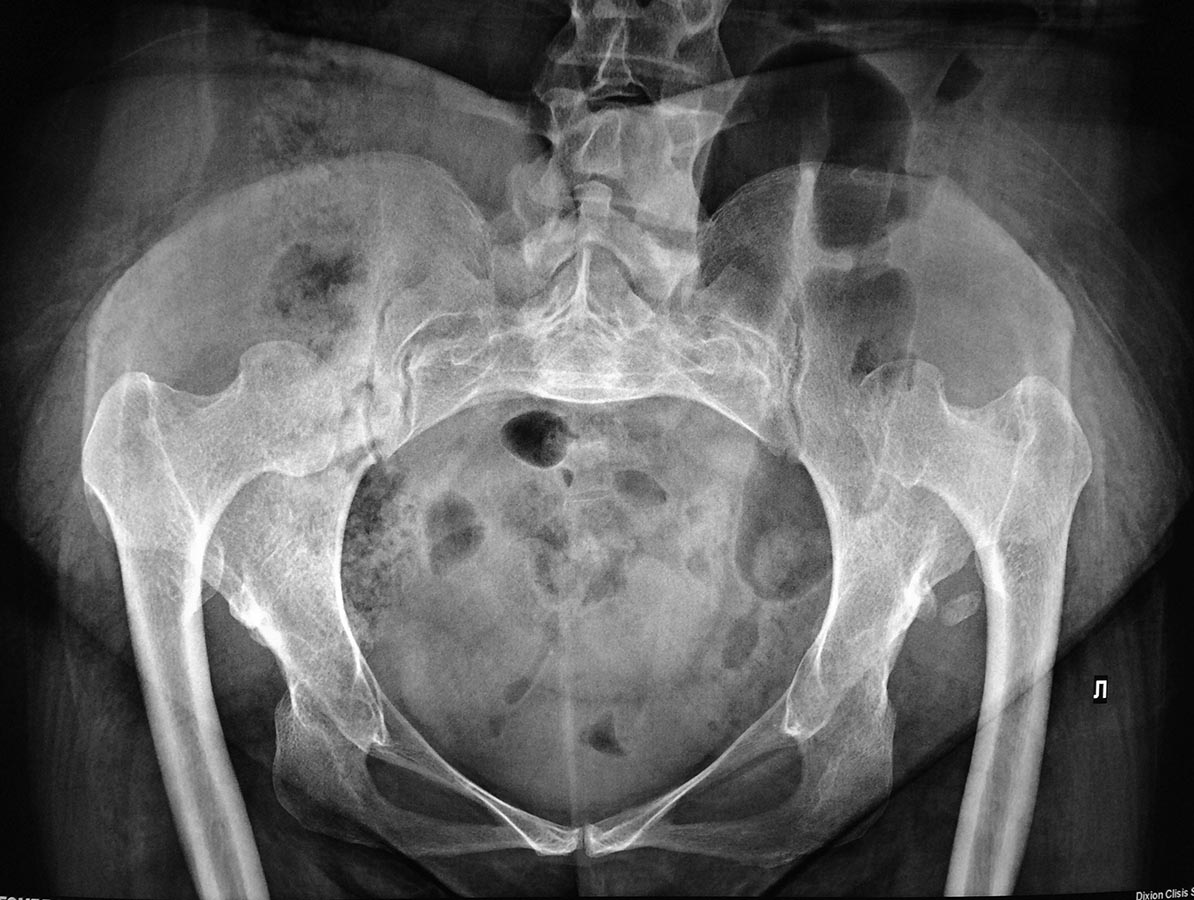

Врожденный вывих бедра

Пациентка 1967 г.р., работает библиотекарем, ходит самостоятельно с опорой на трость.

Жалобы на боли в области тазобедренного сустава слева. Боли впервые появились около 3х месяцев назад. Лечение до появления болевых ощущений не получала. Выраженное ограничение движений в т/б суставах, осевая нагрузка на левую н.конечность вызывает болезненность в области т/б. Куда можно отправить на операцию? Желательно по квоте.